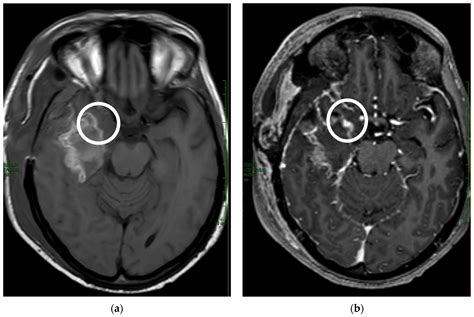

Abscess otak adalah kumpulan nanah di dalam otak. Abscess otak dapat disebabkan oleh bakteri, jamur, atau parasit. Bakteri yang paling sering menyebabkan abses otak adalah Staphylococcus aureus dan Streptococcus pneumoniae. Abscess otak dapat menyebabkan berbagai gejala, termasuk demam, sakit kepala, mual, muntah, kejang, dan perubahan perilaku.

Diagnosis infeksi otak dapat ditegakkan melalui pemeriksaan fisik, pemeriksaan laboratorium, dan pemeriksaan pencitraan. Pemeriksaan laboratorium yang dapat dilakukan meliputi pemeriksaan darah, pemeriksaan cairan serebrospinal, dan pemeriksaan kultur. Pemeriksaan pencitraan yang dapat dilakukan meliputi MRI (Magnetic Resonance Imaging) dan CT scan (Computed Tomography).